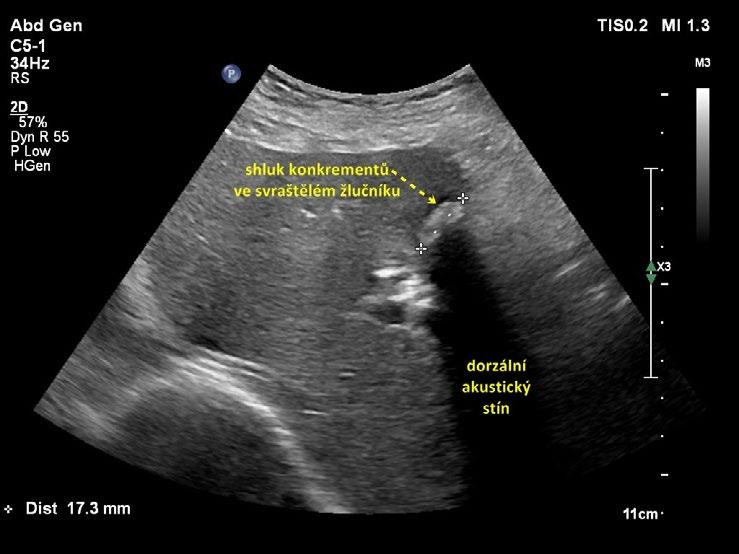

• svraštělý žlučník vyplněný konkrementy (obr. 1.13, obr. 1.14). Lumen ani stěna žlučníku nejsou patrny, v místě žlučníku je shluk konkrementů s dorzálním akustickým stínem. Tento nález je někdy popisován jako „nepřímá známka cholecystolitiázy“, protože pouze z lokalizace konkrementů v typickém místě uložení žlučníku lze dedukovat, že jde o cholecystolitiázu;

Obr. 1.14 Svraštělý žlučník vyplněný litiázou